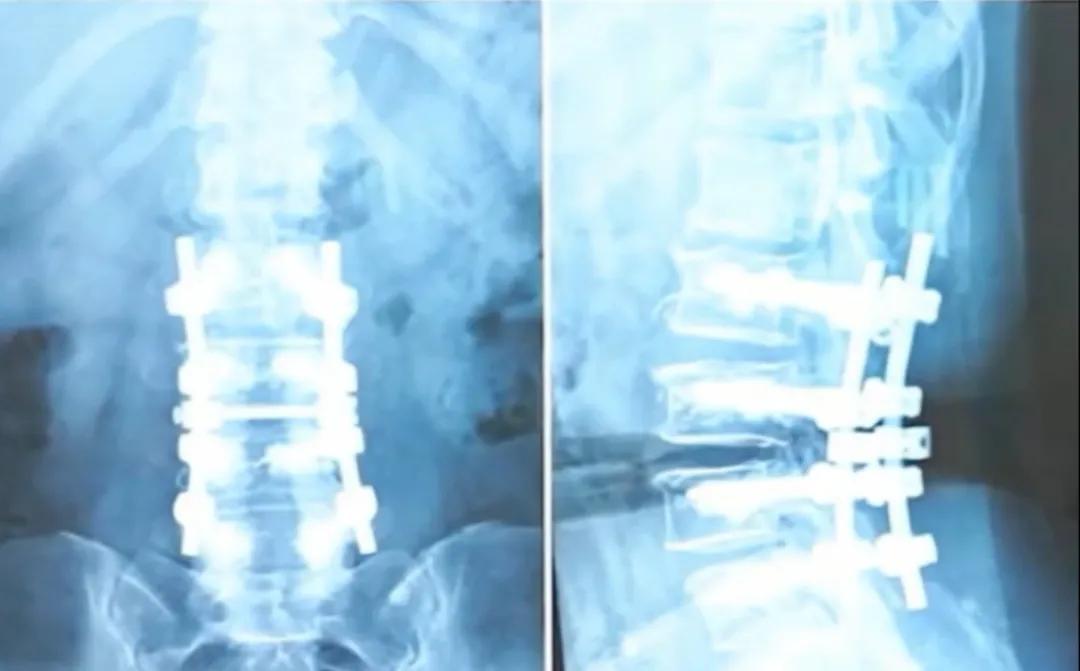

動画で紹介されている50代の患者さんの例のように、重度の脊柱管狭窄症と骨粗鬆症のために手術治療を受けました。脊柱の安定性を維持するため、王主任は彼女の腰椎に4対(計8本)のスクリューを挿入し、骨セメントを用いて椎体を強化しました。このような手術は「大がかり」に聞こえるかもしれませんが、驚くべきことに、術後も彼女の腰椎の柔軟性は良好で、両手を地面につけることさえできました。